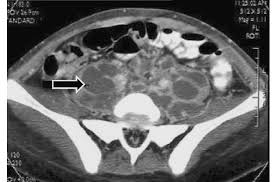

Epiploic Appendagitis